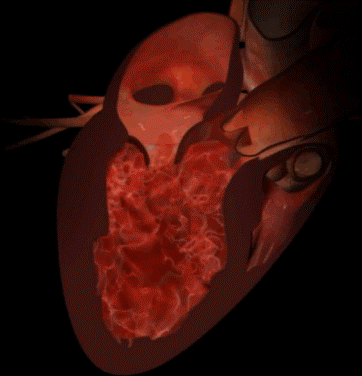

Avaliação Ecocardiográfica de Insuficiência Mitral

Avaliação Ecocardiográfica de Insuficiência Mitral Severa